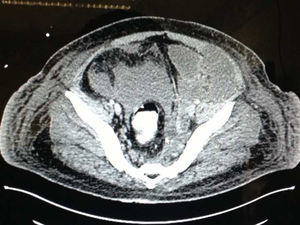

Presentación del casoPaciente masculino de 23 años de edad quien 3 meses antes de su ingreso tras ingesta etílica comienza con epigastralgia intensa, tipo urente, intermitente, localizada, que disminuye parcialmente y se exacerba 10 semanas después del inicio del padecimiento actual asociada a intolerancia a la vía oral, fiebre, astenia, adinamia, dificultad respiratoria e ictericia. Acude a hospital de segundo nivel en donde se le realiza LAPE por abdomen agudo, encontrándose datos de pancreatitis necroticohemorrágica. Únicamente se le colocan drenajes tipo penrose y se le envía a nuestra unidad hospitalaria, ingresando a UCI con Hb 7.8, GB 20mil, Ptl 273, creatinina 3.6, urea 201, glucemia 292, BT 2.7, BD 1.2, BI 1.5, PCR 36.7, DHL 2066, amilasa 36 y lipasa 5,840; tomográficamente con Balthazar D (figs. 1 y 2), asociado a presencia de líquido retroperitoneal izquierdo que se dirige en dirección descendente hasta llegar a cavidad escrotal a través de canal inguinal ipsilateral (figs. 3–5). Se inicia manejo integral del paciente, sin embargo 5 días después de su ingreso, se documenta aumento de volumen escrotal izquierdo, con cambio de coloración y temperatura; se nos interconsulta y se corrobora hallazgo asociado a salida espontánea de material café achocolatado, sanguinolento, inodoro escaso (fig. 6), decidiéndose debido a inestabilidad del paciente y mediante el uso de anestesia local incisión de rafé y drenaje escrotal izquierdo, obteniéndose 450cc de material de características antes mencionadas (fig. 7), con teste macroscópicamente normal, con zonas de necrosis de pared escrotal (fig. 8), y se documenta permeabilidad de canal inguinal, colocándose drenaje tipo penrose, que se mantiene durante 2 días, drenando aproximadamente 600cc de líquido anteriormente mencionado, siendo un total de 1,050cc. El líquido escrotal obtenido reportaba lipasa de 1,834 con cultivo negativo de dicho material. Se deteriora el estado clínico del paciente, presenta falla orgánica múltiple y finalmente fallece.